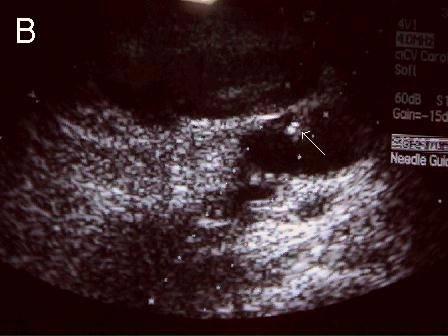

A 连接三联管及穿刺针准备 B 超声引导下注射针进入瘤腔底部(箭头处) C 经注射针注入盐水出现超声频闪现象; D 远端瘤腔内血栓逐渐形成; E 远端、近端瘤腔内血栓完全形成; F 术后足背动脉血流良好. 国内首家开展,例数最多,疗效肯定。此技术在全国推广应用。处于全国领先水平。